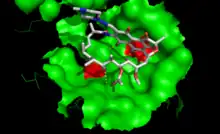

Mutation de la cible de l'antibiotique

Chaque antibiotique agit en se fixant sur une cible précise dans la cellule : paroi, ribosome... La présence d'une modification consécutive à une mutation modifie le site de fixation et empêche ainsi la liaison de l'antibiotique. C'est un des mécanismes de résistance à la streptomycine, l'un des premiers antibiotiques utilisés pour traiter la tuberculose. C'est aussi l'un des principaux mécanisme de résistance à la rifampicine qui est l'un des antibiotiques qui a remplacé la streptomycine. On observe des mutations de l'ARN polymérase bactérienne qui bloquent la liaison de la rifampicine. Les acides aminés mutés sont situés à proximité immédiate du site de fixation (voir figure à droite).